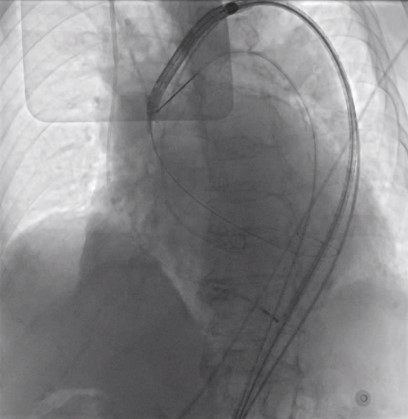

Under local anesthesia and conscious sedation, femoral arteries (FA) were accessed by 8-Fr sheath at right FA and two of 8-Fr sheaths at left FA for pigtail catheter and snare-assisted device. Aortography was conducted by pigtail catheter to locate aortic cusp. An Amplatz left catheter over a 0.035-inchJ-tip wire was placed at aortic cusp via the RFA which was then exchanged with an Amplatz Super Stiff wire to upsized 16-Fr Braidin sheath. The aortic valve was crossed with an Amplatz left catheter over a straight-tip wire under cuspoverlap views (LAO16, CAU 30), peak-to-peak gradient of 19 mmHg. During RV pacing, a Safari Extra Small guidewirewas positioned in LV and the AV was pre-dilated by an 18 × 40 mm Alwide balloon. Subsequently, a 27 mm VitaFlow valve was deployed in an optimal position under snare-assisted. Post-deployment aortography revealed mild AR, LVEDP of20 mmHg, and 4 mmHg of LVOT gradient. Post-dilation was performed by a 24 × 40mm VACC III balloon. The FA was closed by 6-Fr Proglide at the right and 8-Fr AngioSeal at the left. Post-TAVR TEE showed mild PVL without significant transvalvular gradient and preserved LVEF of 64%. One-month after the TAVR, she was diagnosed with early-stage colonic cancer. A laparoscopic hemicolectomy which completed pre-operative evaluation, coronary revascularization, TAVR and appropriated medication was performed as time-sensitive surgery following by CMT with curative intent.